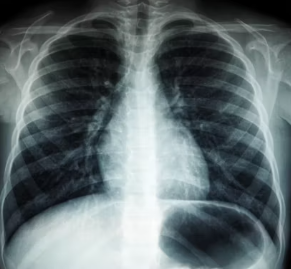

이 외에 흉부 X-ray 또는 CT를 통해 폐기종 변화나 다른 폐 질환 유무를 확인하고, 혈액 검사로 알파-1 항트립신 결핍증과 같은 특정 원인이나 합병증을 평가하기도 합니다. 의료진은 이러한 검사 결과를 종합하여 만성폐쇄성 폐질환의 진단과 중증도를 판단합니다.

만성폐쇄성 폐질환은 만성적인 경과를 보이는 질환이므로, 꾸준한 모니터링과 정기 검진이 매우 중요합니다. 주기적으로 폐기능 검사, 흉부 X-ray, 혈액 검사 등을 통해 폐 기능의 변화와 합병증 발생 여부를 확인해야 합니다.